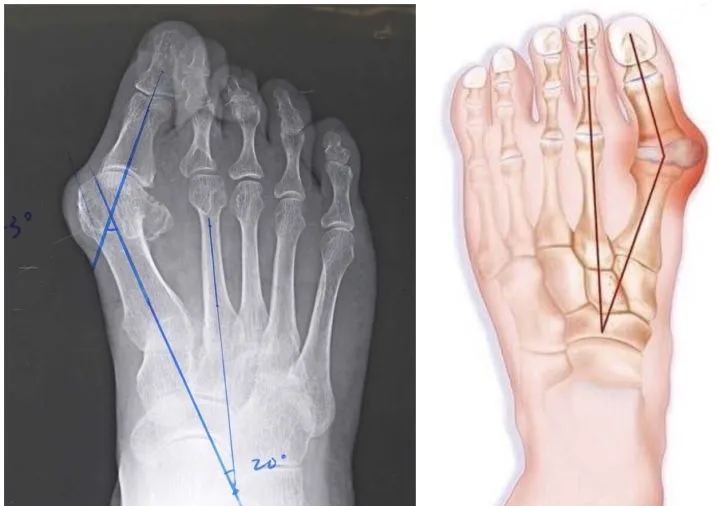

倘若再配上窄鞋头,脚趾头严重受到挤压、弯曲异常,还会加剧「拇外翻」的形成。

X 线片中可明显看到踇外翻的结构改变